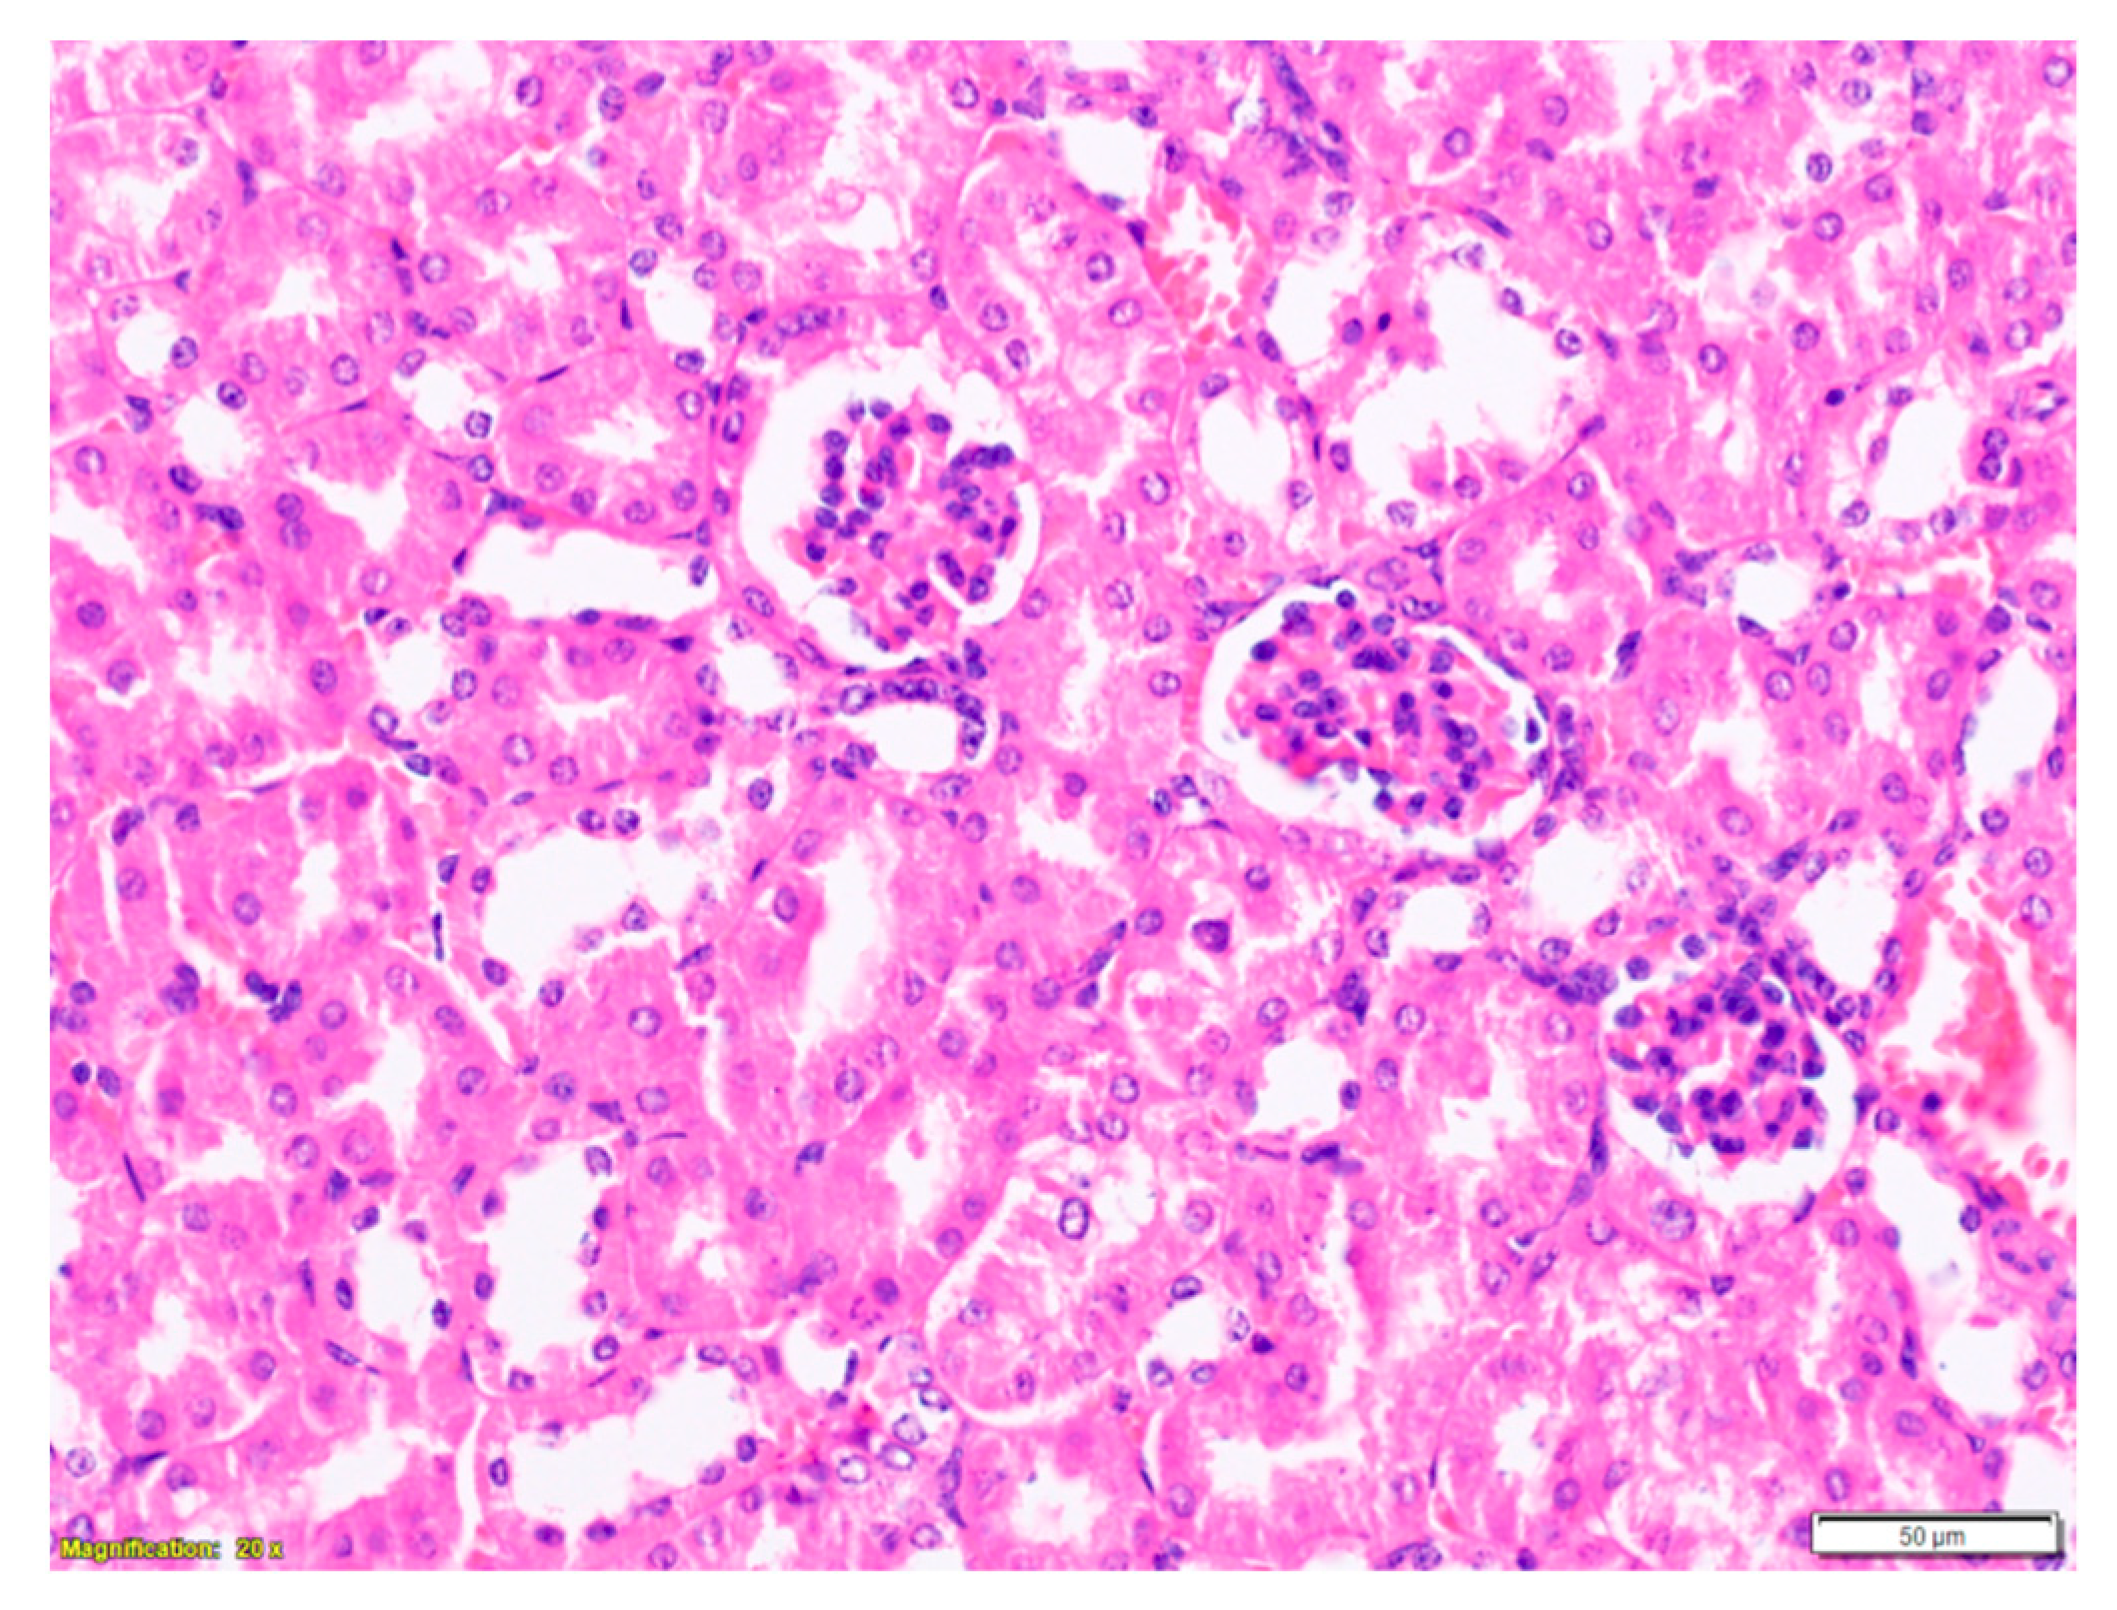

2.3. Purified LysM Lectin Impact to Kidney Morphology

3. Discussion

4.5.3. Histological Analysis of Kidney Samples